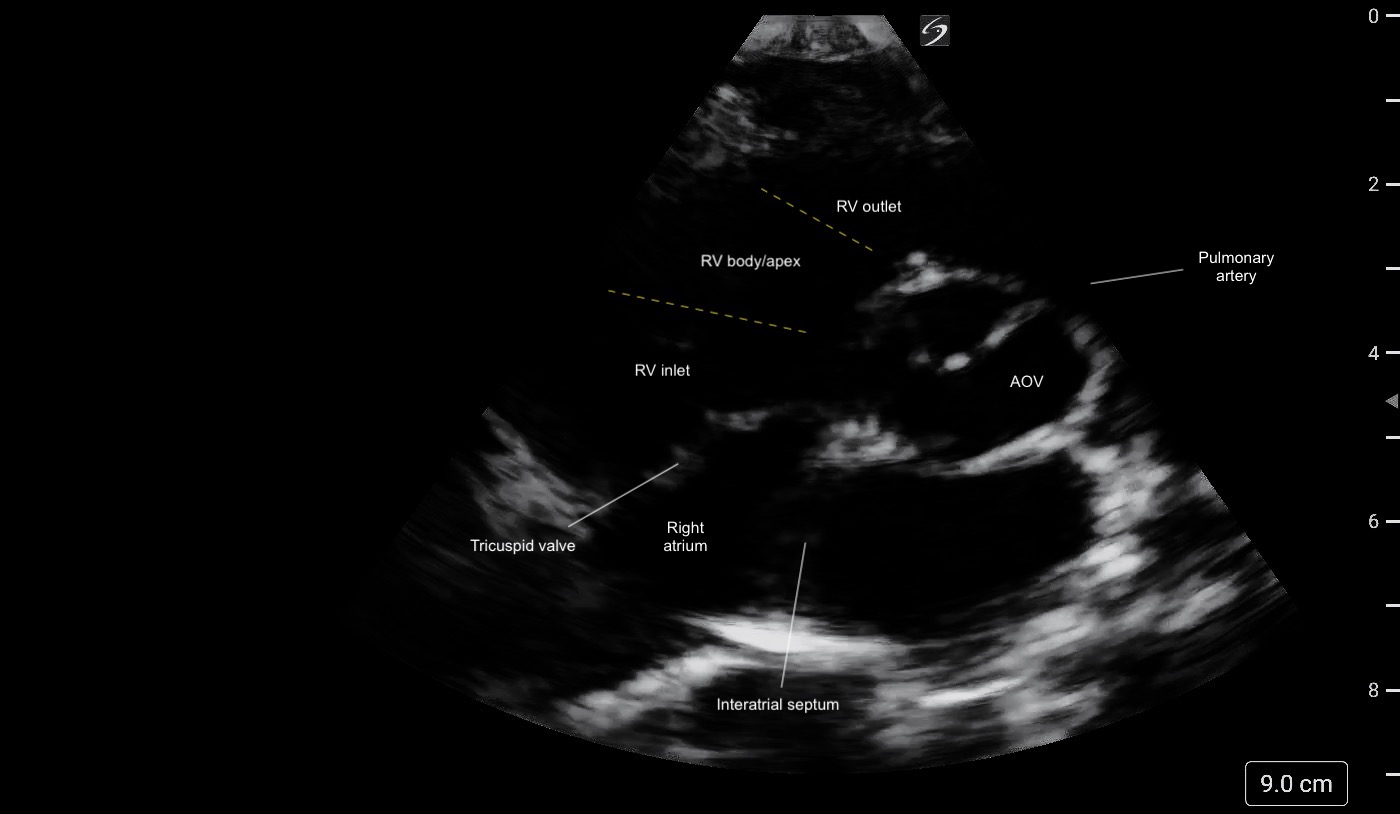

Parasternal Short Axis

What am I Looking at?

The PSAX view provides a cross-sectional image of the LV, allowing simultaneous visualization of multiple walls. It is the preferred view for global assessment of LVfx and RWMAs. This view is useful for assessing wall motion across the anterior, lateral, posterior, inferior, and septal segments, all seen in a single plane at multiple levels (basal, mid, apical) (figure 11).

A circular LV cavity indicates you’re on-axis, while an oval or elliptical shape suggests you’re off-axis and should adjust your probe angle for a true short-axis view.

Figure 11. PSAX at the mid-papillary level with left ventricular walls labeled.